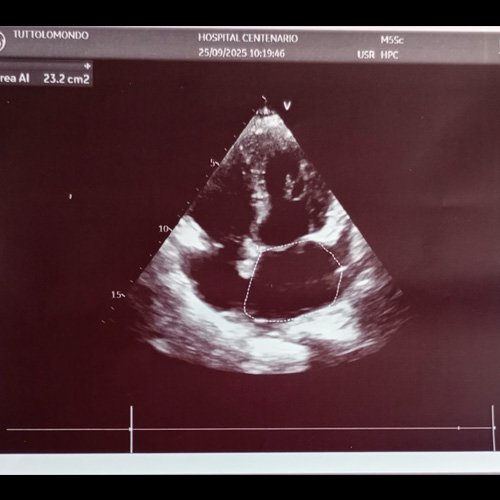

• Ecocardiograma doppler (Dia 31): VI dilatado en grado leve. Disquinesia de los segmentos apicales (anterior, inferior, lateral, septal) y de los segmentos medios (anterior, anteroseptal, inferoseptal, inferior, infralateral y anterolateral). Hipermotilidad de los segmentos basales. FSVI  deprimida en graso severo. AI dilatada en grado leve. Área 23 cm2. FEVI ESTIMADA 25-30%. VD de dimensiones normales con los segmentos medios y apicales de la pared lateral e hiperquinesia de segmento basal. Índice de función sistólica deprimido (TAPSE 9mm) Strain de la pared libre del VD muy reducido 6%. Aurícula derecha de dimensiones normales. Ecogramas valvulares sin alteraciones significativas. Válvula aórtica trivalvar. Raíz aórtica de dimensiones normales. Aorta ascendente y cayado aórtico normal. Pericardio con derrame leve. Vena cava dilatada con colapso inspiratorio reducido. Válvula mitral: flujo pseudonormal. Disfunción diastólica grado II, con aumento de las presiones de llenado. Relación E/e 19. Sin reflujo. Aórtico: flujo de morfología y velocidad máxima normal. Sin reflujo. Tricuspídeo: flujo de morfología y velocidad máxima normal. Reflujo leve que permite estimar una PSAP de 45 mmHg. Pulmonar: flujo de morfología y velocidad máxima sin reflujo.  Conclusiones: los hallazgos imagenológicos sugieren miocardiopatía de Takotsubo en primera instancia (por trastorno de la contractilidad parietal que se extiende más allá del territorio de irrigación de una arteria coronaria) con compromiso que afecta no solo del ventrículo izquierdo sino además el derecho.

En el día 30 por presentar dolor de pecho de características atípicas y disnea, alteraciones electrocardiográficas (T negativas en derivaciones precordiales: V2 a V6) y ecocardiograma alterado con fracción de eyección global deprimida en grado severo y hallazgos imagenológicos sugerentes de miocardiopatía de Takotsubo, fue evaluada por el Servicio de Cardiología quienes inician tratamiento con furosemida y balance hídrico negativo, con buena respuesta.

Se presenta el caso de una paciente con antecedente de HIV diagnosticado hace más de 30 años, con control regular de su enfermedad. Presentó una internación previa en el año 2023 por debut de insuficiencia cardíaca con FEY disminuída (40%) con sospecha de etiología asociada a HIV (miocardiopatía dilatada) por cardiorresonancia de ese mismo año. Actualmente cursa internación para estudio de síndrome constitucional de más de 3 meses de evolución, con resultado de biopsia hepática hace 1 mes que informó proceso granulomatoso crónico con hallazgo de múltiples bacilos ácido-alcohol resistentes fragmentados, especias de Histoplasma Capsulatum e inclusiones intranucleares con cambios citopáticos vinculables a Citomegalovirus. Durante la misma intercurre con episodio de insuficiencia cardíaca con hallazgo ecográfico altamente sugestivo de Síndrome de Takotsubo.

Ecocardiograma (Dia 31)